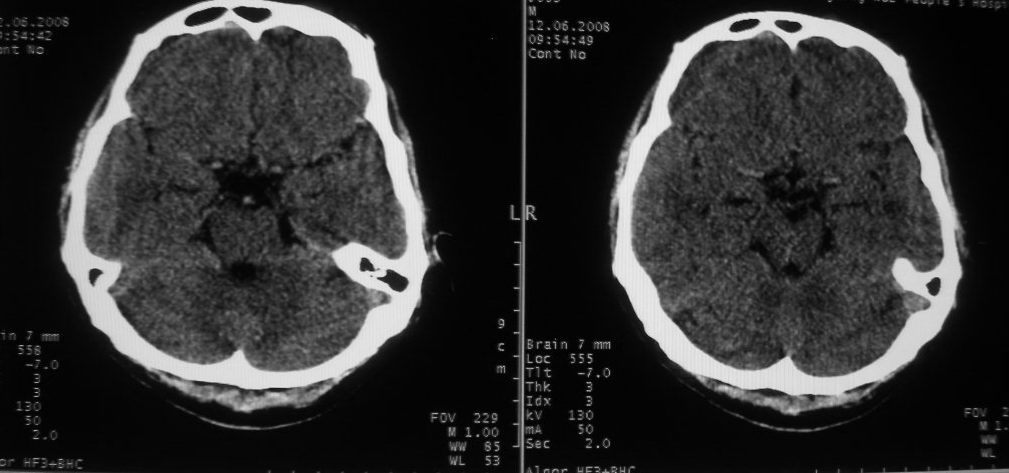

以下是引用守望可可西里在2008-6-13 1:25:00的发言:[br][br] 1.双侧大脑中动脉高密度踌型样接近于全程显示,部分大脑前动脉、基底动脉也呈高密度改变。[br] 2.右侧基底节多发类圆形ct值接近于出血的高密度,边缘模糊。双侧小脑幕及直窦、上矢状窦增宽、模糊。左侧横窦和乙状窦区密度增高、呈云雾状,内缘模糊。[br] 如果这样的表现发生在一个老年人脑部,我们首先会想到是高血压、动脉粥样硬化,就可以很容易得出结论。但这发生在一个20岁年青人的身上,且病程长达半年、临床症状不怎么重,这就比较蹊跷且应该引起高度重视了。[br] 我认为此病人应该是一个血液病患者--双侧大脑中动脉、部分大脑前动脉及基底动脉的高密度改变,只是一个假象:即相对于ct值偏低,只有35的脑灰质而言的相对高密度。而那么多出血改变,则是真正的病变表现。[br] 建议临床进一步进行其他相关的血液、骨髓检查,肝、脾也应该好好检查,应有明显的肿大。